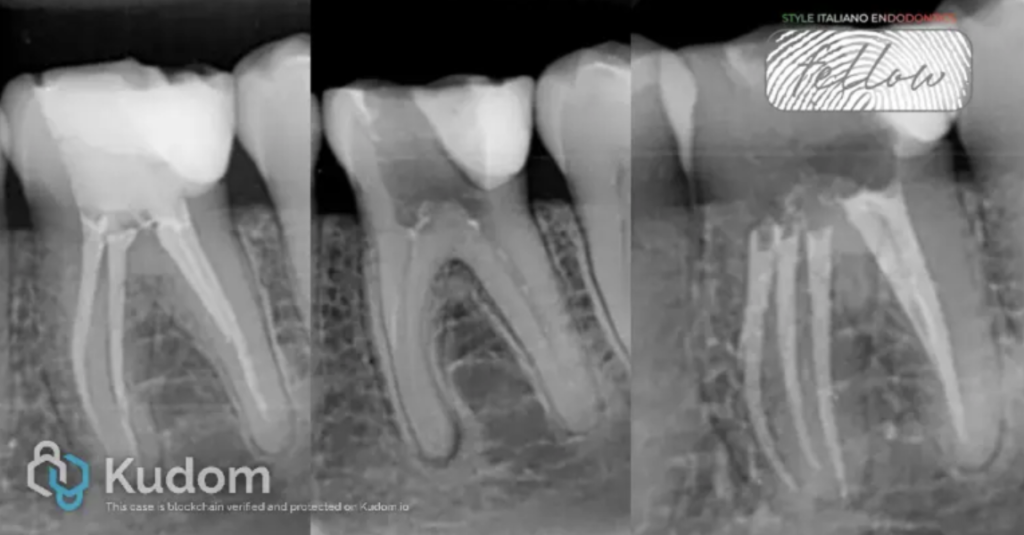

Fig. 1

- Initial Radiograph

Fig. 2

Axial CBCT Slice:The analysis of the axial slice revealed the presence of a third, un-obturated canal in the mesial root of tooth 3.6, consistent with the Middle Mesial Canal

Fig. 4

Master Cone Fitting: The final working length of the three mesial and the distal canals was confirmed using a master cone.

Fig. 5

Fig. 6